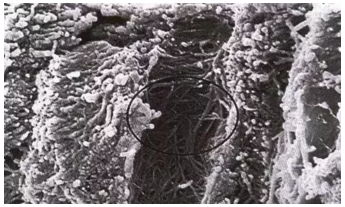

牙本質(zhì)切削后牙本質(zhì)縱斷面,可見牙本質(zhì)小管中存在玷污層栓(放大倍數(shù)2000)

牙本質(zhì)縱斷面。管周牙本質(zhì)被去除,管間牙本質(zhì)膠原纖維暴露(放大倍數(shù)5000)